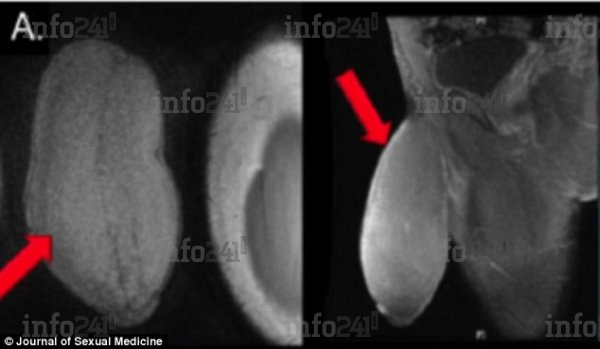

Ses organes génitaux aux rayons X

L’opération a été effectuée à la demande du jeune homme dont le membre mesurait près de 18 cm de long au repos, avec une circonférence de 25 cm, ce qui lui donnait l’apparence d’un « ballon de football américain » selon les chirurgiens qui l’ont examiné. Un format hors norme qui l’empêchait d’avoir des rapports sexuels et de pratiquer certains sports. En outre, l’adolescent souffrait également de priapisme, un trouble qui provoque des érections involontaires.